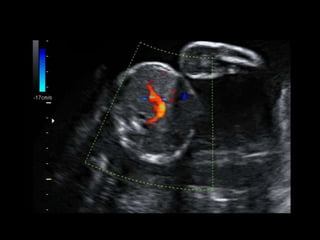

• 36 yo female 30.5 weeks pregnant

• Referred with ‘multiple fetal anomalies’ for

fetal ultrasound

LUS – Cephalic

POSTNATAL BABYGRAM

• What are the findings?

• What is the diagnosis?